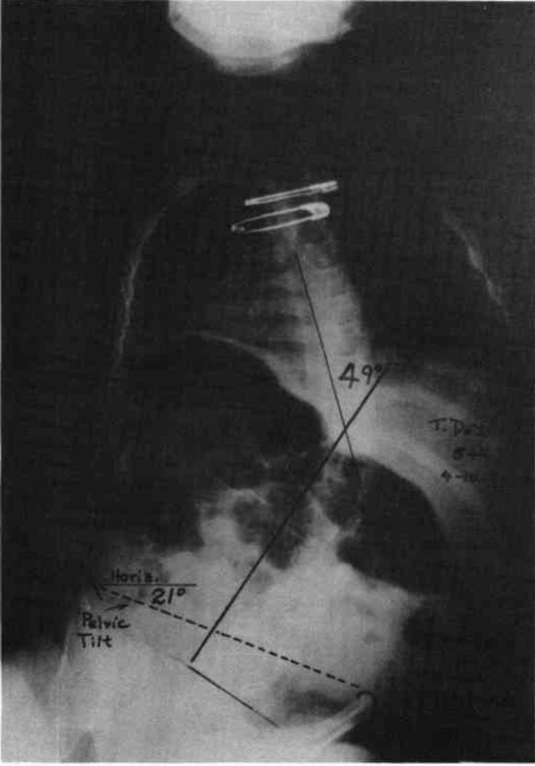

Figure 7. The diagrams on the left illustrate the similarity between the spinal column in the case of an uncontrolled pelvis and the slender column pin-jointed (free to tilt) at its lower end. The two diagrams on the right illustrate the similarity between the controlled pelvic case and the built-in base end condition.To fully appreciate the strength of this scheme in practice, compare the two x-rays in Fig. 8a and Fig. 8b. Fig. 8a is the x-ray taken just before the pelvic leveling procedure was performed and Fig. 8b is the x-ray taken a few minutes later, after the pelvic leveling procedure was performed. The Cobb angle is reduced from 36 degrees to 20 degrees by this quick procedure, which is normally performed as a routine part of positioning the child in the sitting support orthosis. These x-rays are of a boy with Duchenne Muscular Dystrophy; he was not wearing a corset.

Figure 8a. An x-ray taken just before the pelvic leveling procedure was performed.Figure 8b. The x-ray taken a few minutes later after the procedure.